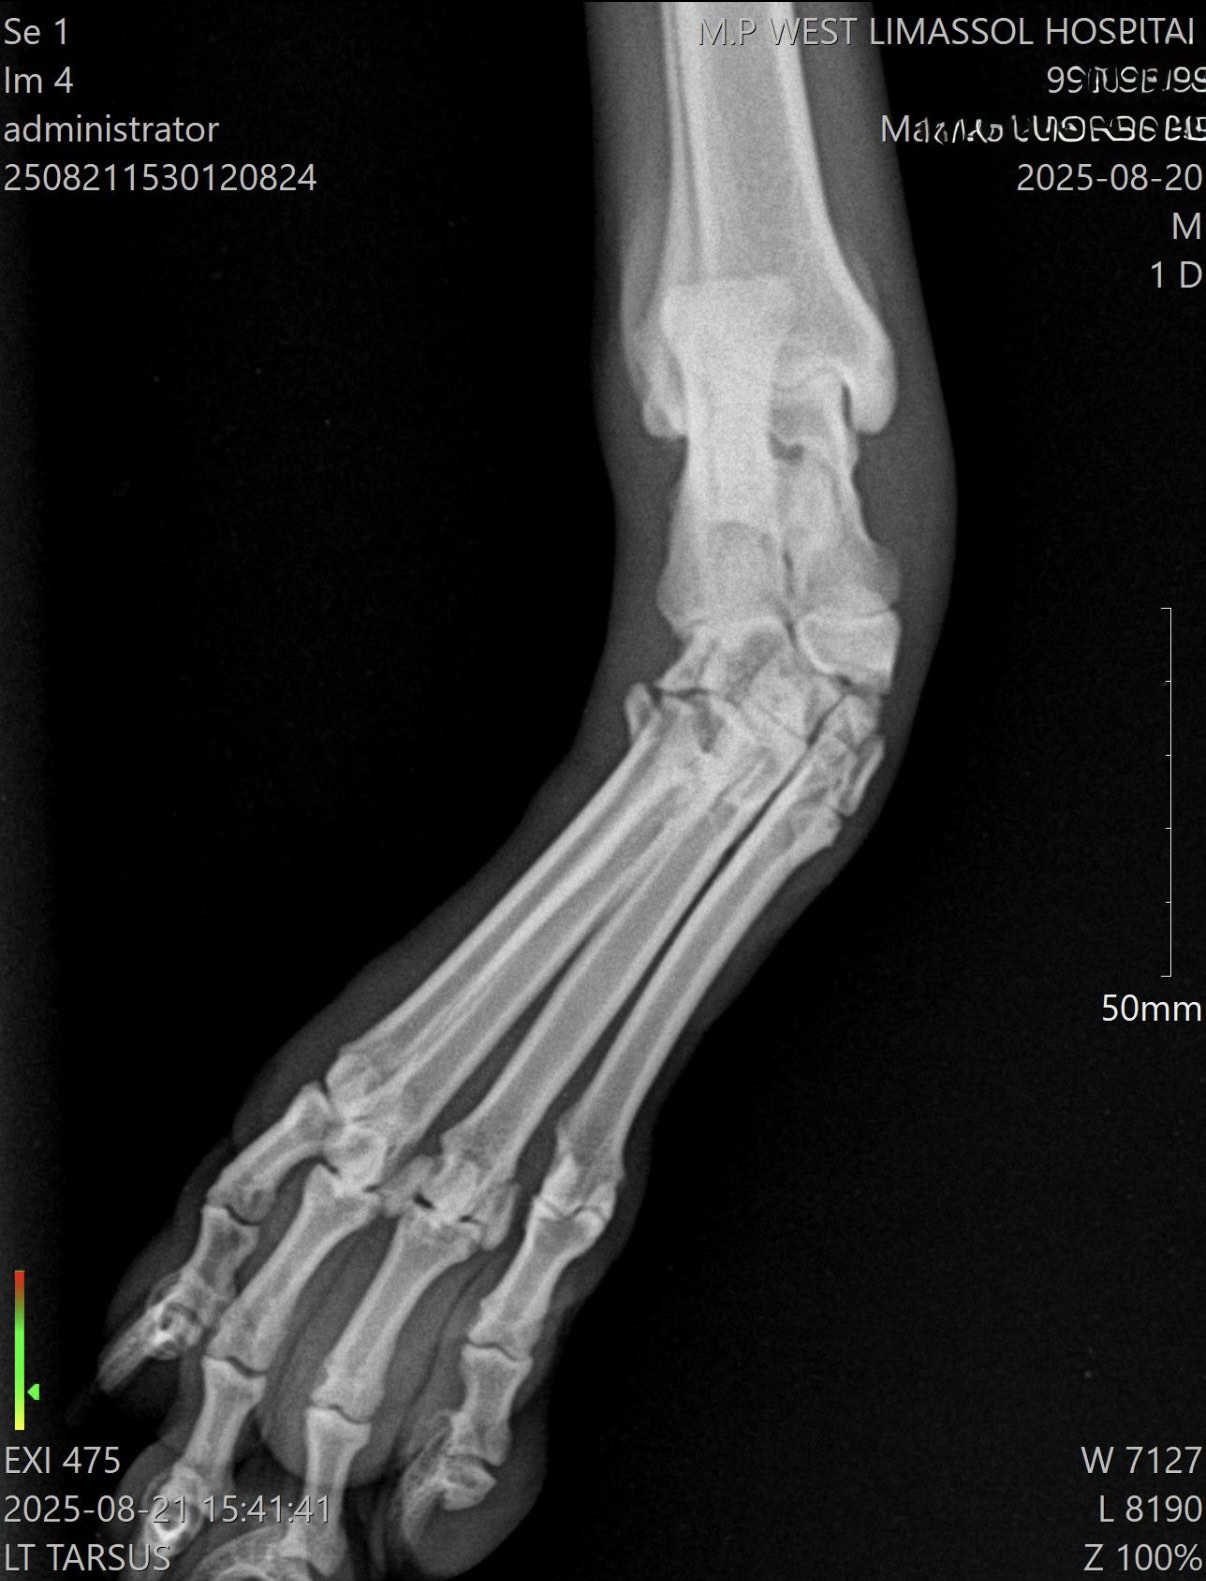

Ένας νεαρός, δραστήριος σκύλος κυνηγιού προσκομίστηκε μετά από βίαιο τραυματισμό κατά τη διάρκεια εργασίας. Κατά την κλινική εξέταση παρατηρήθηκε έντονο οίδημα, αστάθεια του ταρσού και έντονος πόνος κατά την κινητοποίηση. Η ακτινολογική εξέταση, σε συνδυασμό με Αξονική Τομογραφία (CT), ανέδειξε πολλαπλά κατάγματα σησαμοειδών μεταταρσίου καθώς και πλήρη ρήξη των έσω πλάγιων συνδέσμων. Λόγω της σοβαρής αστάθειας, η συντηρητική αγωγή κρίθηκε ακατάλληλη.